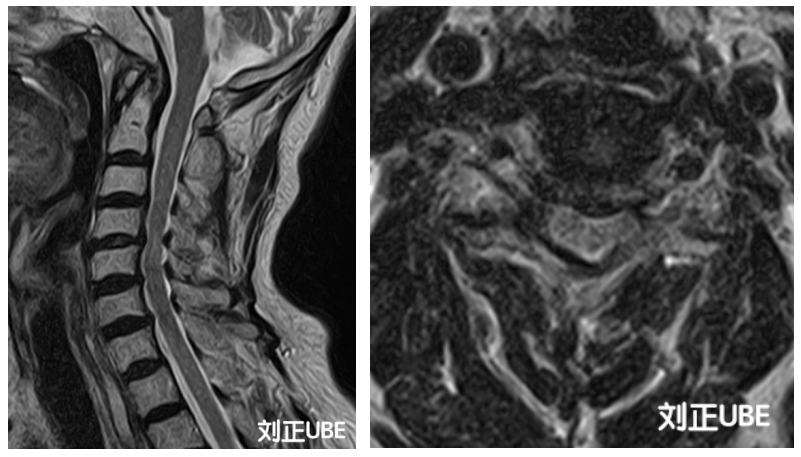

术后颈椎MRI提示受压节段减压充分